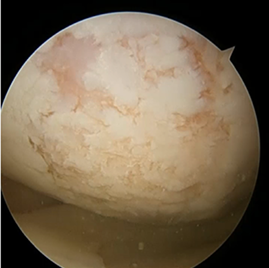

수술 전후 사례

수술 전

카티스템 수술

수술 후 1년

카티스템 줄기세포 연골재생술(Cartistem)

제대혈 유래 줄기세포 치료제(카티스템)은 큰 연골손상이나 퇴행성 관절에서도 적용 가능하며, 더 질 좋은 연골 재생을 기대하는 수술입니다.

1관절경 또는 최소 절개로 손상된 연골을 깨끗하게 다듬는다.

2이식부위를 형성

3줄기세포 제제(카티스템)를 병변 부위에 채워 넣고 고정 한다.

4봉합후 마무리 한다. 줄기세포가 더 질이 좋은 연골(유리연골 유사 조직)을 형성하도록 도와준다.